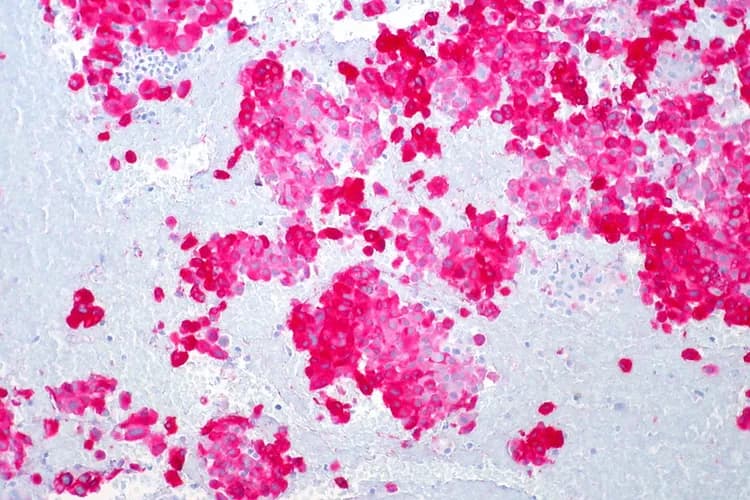

In the new paper, the researchers combined CyCIF imaging data with 3D high-resolution microscopy and fine-scale RNA sequencing to create maps capturing where cells are located and how they interact as normal tissue morphs into melanoma.

"We're able to see everything from normal skin to early lesions to invasive melanoma, sometimes all in one piece of tissue," Santagata said. "You end up with this map of how melanoma is developing right in front of you."

The maps reveal what Santagata describes as "the battle between tumor cells and immune cells" that results in melanoma succumbing when immune cells are victorious, and melanoma progressing when tumor cells win.